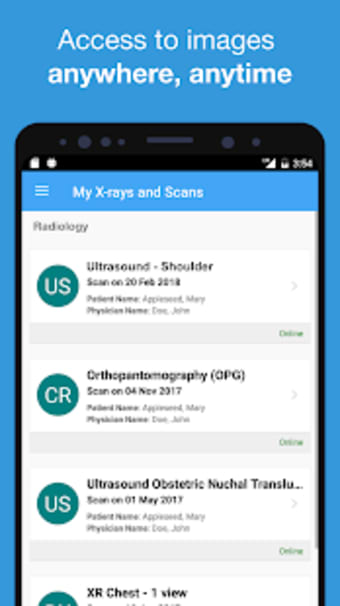

Met Affidea Connect Patient kunt u uw beeldvormingsresultaten bekijken, ze delen met uw zorgverleners en overal en altijd toegang krijgen. De app is gemakkelijk te gebruiken en u kunt er zonder moeite doorheen navigeren. U kunt ook eerdere beeldvormingsresultaten bekijken, waardoor het gemakkelijker wordt om uw voortgang te vergelijken en bij te houden. Over het algemeen is Affidea Connect Patient een geweldige app die u helpt om de controle te houden over uw gezondheidszorg en geïnformeerde beslissingen te nemen over uw gezondheid.